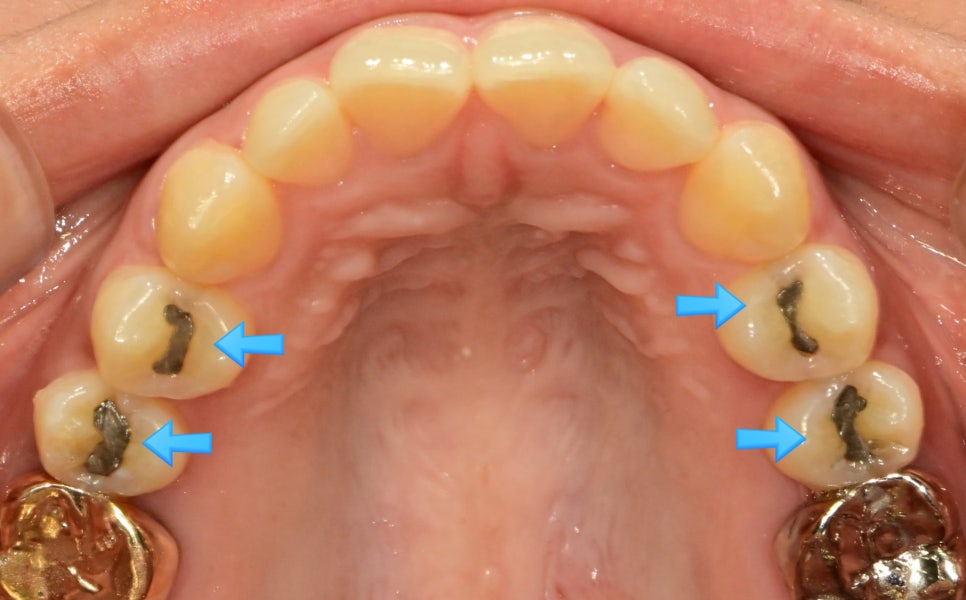

상악 교합면 사진 — 4개 치아에 아말감 충전물이 파란 화살표로 표시된 before 임상 사진

▲ 아말감으로 충치 치료를 여러 개 받으신 환자분의 상악 교합면